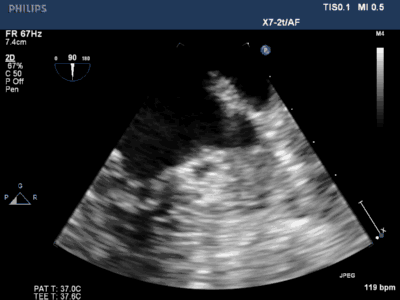

食道超声医生:钟桃娟医生、梁逸伦医生

3. 经右侧股静脉置入SL1鞘管,沿鞘管送入房间隔穿刺针,食道超声下见左心耳血栓

4. 超声指导下成功行房间隔穿刺,将鞘管推进至左房后予肝素7000U,SL1 导丝送左房后,超声下测左心耳开口大小后选用LAmbre 左心耳封堵器(20-26mm)

5. 超声及造影下见封堵器放置位置良好,二尖瓣及肺静脉段未见影响,测试位置固定后释放封堵器